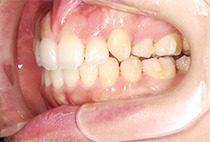

出っ歯と前歯のガタつきにお悩みだった20代女性の症例です。

金属アレルギーがあるため、メタルフリーで治療できる【インビザライン】による抜歯矯正を選択されました。

前歯のガタガタ、中心のずれ、顎のずれ、外科矯正は避けたい

叢生、左右非対称咬合